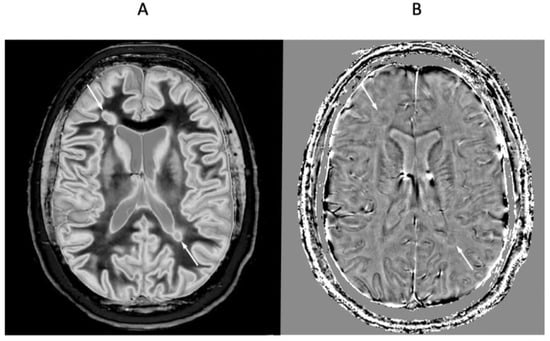

Figure 6 shows mid-ventricular images of a 41-year-old female patient with MS in remission. No abnormality is seen on the T2-wSE image (Figure 6A). On the narrow mD dSIR image (Figure 6B), normal peripheral white matter is dark and has a low signal (thick arrows). The more central superior longitudinal fasciculi show a higher signal with a gradient of signal decreasing from posterior to anterior. Within them are the corticospinal tracts (short thin arrows). Three focal lesions are seen in the peripheral white matter and at the leucocortical junctions (long thin arrows).

Figure 6.

Forty-one-year-old female with MS in remission. Comparison of 2D T2-wSE (A) and narrow mD dSIR (B) images. No abnormality is seen on the T2-wSE image, but three focal lesions are seen on the dSIR image (long thin arrows). The corticospinal tracts are also seen (short thin arrows). The normal superior longitudinal fasciculi are of intermediate (posterior) to low (anterior) signal in (B). More peripheral white matter is normal and has a low signal in (B) (thick arrows). A high signal boundary is seen between white matter and cortical grey matter as well as between white matter and CSF around the lateral ventricles in (B).

At a supraventricular level in the same patient (Figure 7), the T2-wSE image is again normal (Figure 7A). The corresponding narrow mD dSIR image shows only a small region of low signal normal white matter (dark arrow). The corticospinal tracts are seen (short thin white arrows), as well as a lesion (long thin white arrow). There are widespread asymmetric and patchy abnormalities in the white matter.

Figure 7.

Forty-one-year-old female patient with MS in remission (as for Figure 6). Two-dimensional T2-wSE (A) and narrow mD dSIR (B) images at the same level. No abnormality is seen in (A). A focal lesion is seen in (B) (long thin white arrow) and the corticospinal tracts show a high signal (short thin white arrows). In addition, there is widespread, patchy increased signal in white matter (short thick white arrows) with only a small region showing a normal or near normal low signal (long black arrow). High contrast and high spatial resolution contrast are seen at the boundaries between normal white matter and normal gray matter in (B). These features are less obvious in areas where the white matter shows abnormal high signal.